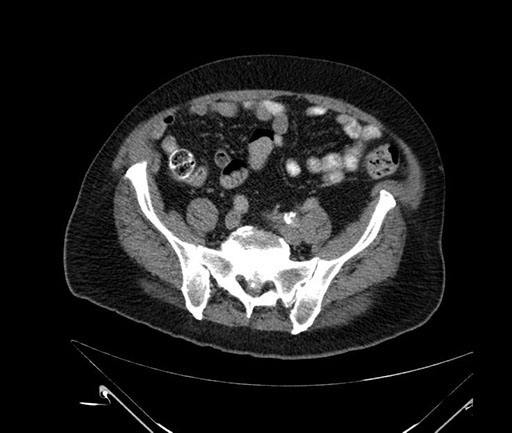

Coronal - stented